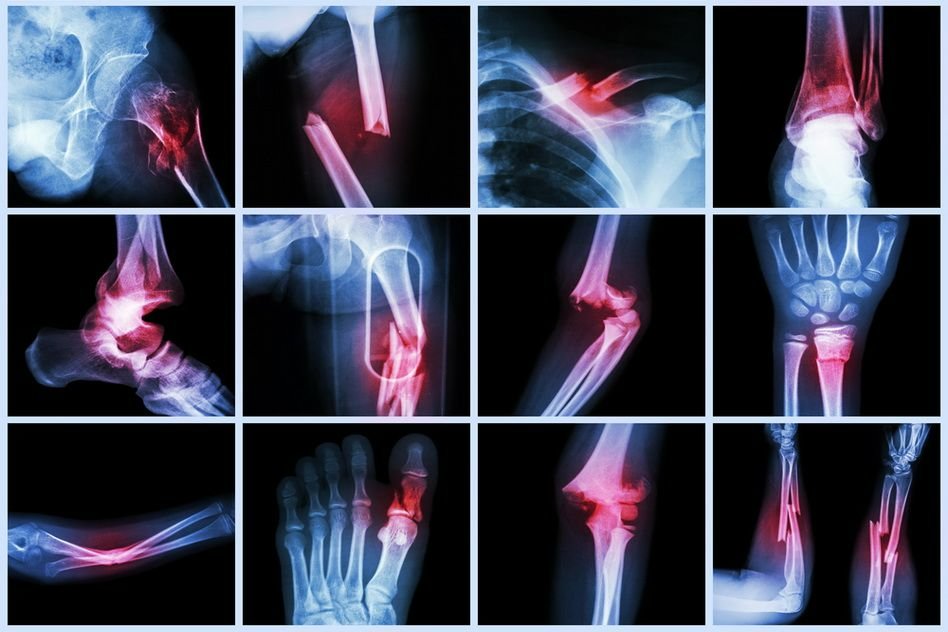

• Examenul radiografic este mijlocul cel mai sigur pentru a pune în evidență o fractură, cu condiția unei bune execuții tehnice. El trebuie făcut sistematic, înaintea oricărei tentative de reducere, și, pentru a fi complet în aprecierea importanței deplasărilor, el trebuie efectuat cel puțin din două incidențe.